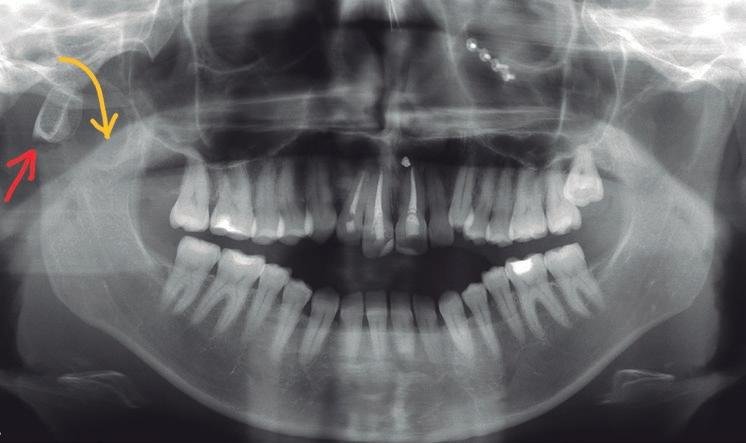

Radiografía A.T.M. Lateral

A.T.M. Lateral

La vista lateral permite evaluar:

• Posición del cóndilo mandibular en la fosa articular

• Apertura y cierre de la articulación

• Desplazamiento anterior del disco articular

• Cambios degenerativos en la articulación